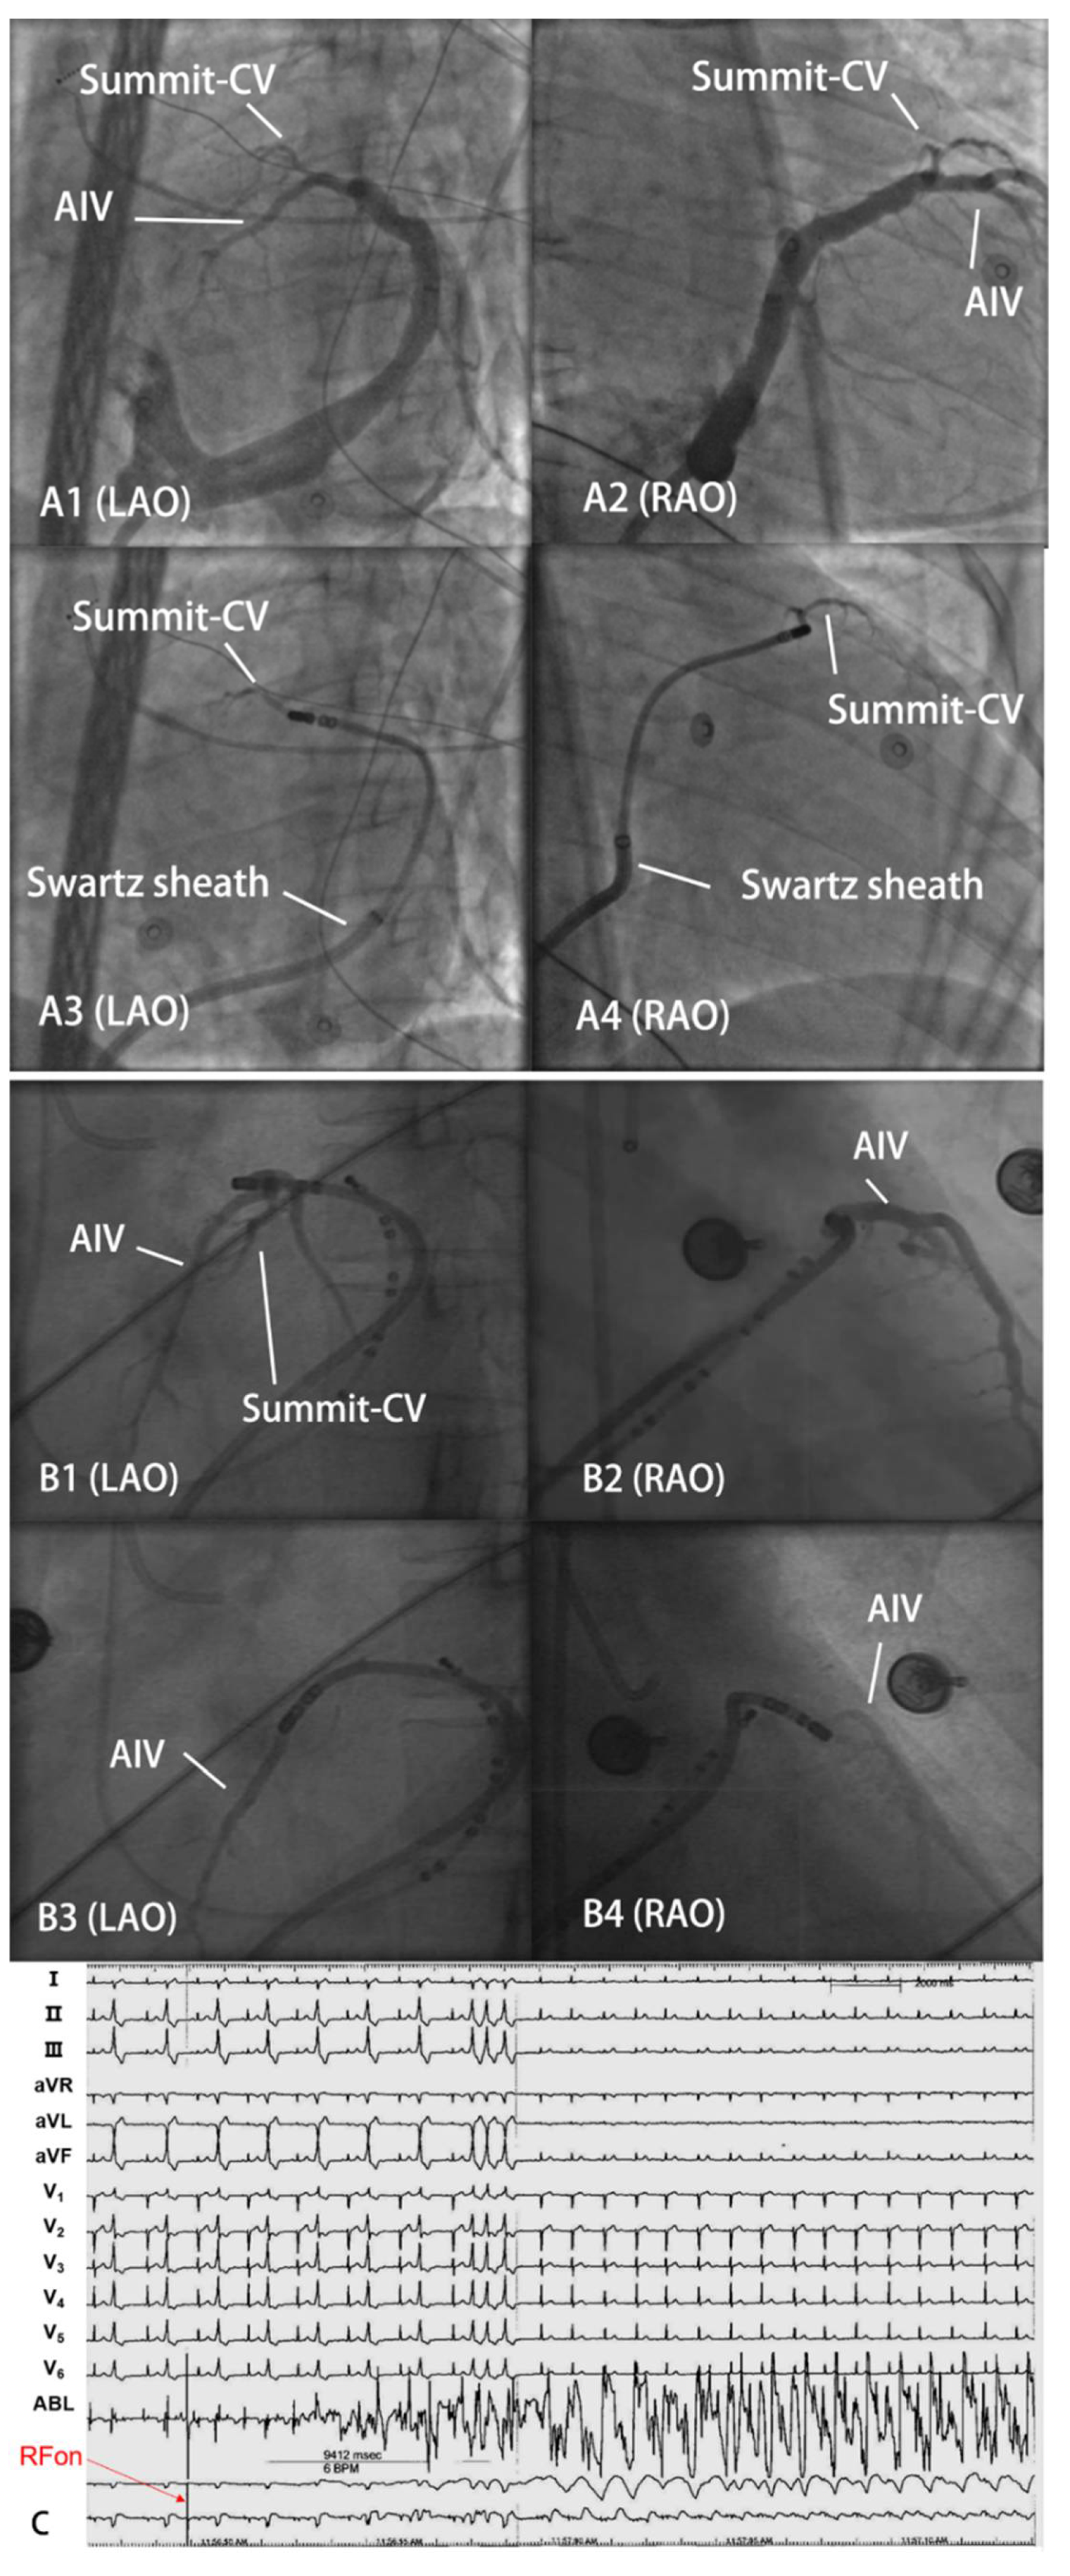

- Zheng, C.; Lin, W.Q.; Wang, Y.J.; Lv, F.Z.; Jin, Q.; Li, J.; Lin, J. Catheter Ablation of Ventricular Arrhythmias Originating From the Region of DGCV-AIV via a Swartz Sheath Support Approach. Front Cardiovasc. Med. 2021, 8, 801441. [Google Scholar] [CrossRef]